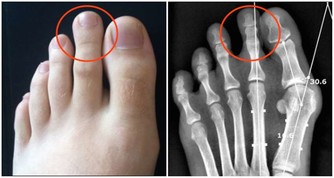

4.護脊椎、防關節退化

在高抬腳時,脊椎保持水平,全身肌肉富有彈性,氣血順暢,各關節自會增生骨髓,脊椎兩旁神經恢復平常傳導作用,何來關節退化,或長骨刺,壓迫神經的病痛呢?